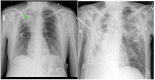

Non-tuberculous mycobacteria (NTM) are ubiquitous environmental organisms that may cause opportunistic infections in susceptible hosts. Lung infections in immunocompetent persons with structural lung disease are most common, while disseminated disease occurs primarily in immunocompromised individuals. Human disease caused by certain species, such as Mycobacterium avium complex, Mycobacterium abscessus, and Mycobacterium kansasii, is increasing in incidence and varies by geographic distribution. The spectrum of NTM disease varies widely in presentation and clinical outcome, but certain patterns can be organized into clinical phenotypes. Treatment options are limited, lengthy, and often toxic. The purpose of this case-based review is to provide non-clinician scientists with a better understanding of human NTM disease with an aim to stimulate more research and development.